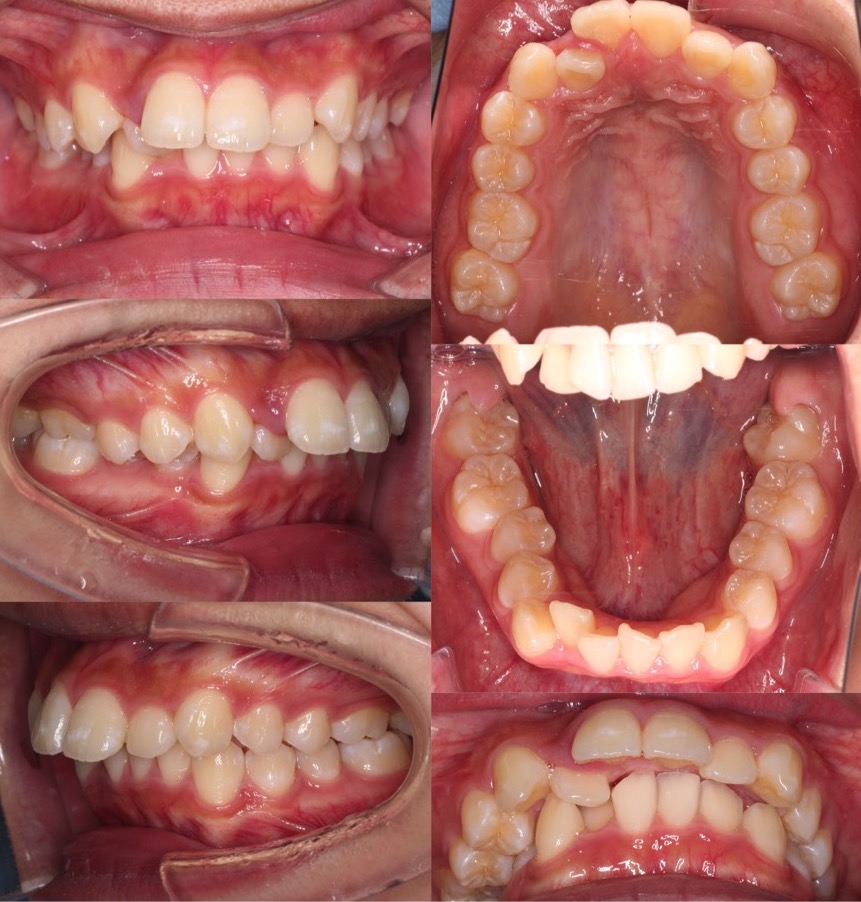

大学生女性・マウスピース型矯正装置・上抜歯

典型的な上のみの抜歯症例です。II級顎間ゴムを使用しながら、ゆっくりと前歯を後方移動させていきました。

<症例概要> 難易度★★★☆☆

主訴:出っ歯

年齢・性別:高校生女性

住まい:千葉県旭市

症状:上顎前突

治療方針:抜歯空隙閉鎖

治療装置:マウスピース型矯正装置(アライナー装置)

抜歯:上左右第一小臼歯(計2本)

治療期間:2年4か月(1週間交換)

アライナー枚数:47+37+16ステージ

リテーナー:上下フィックスタイプ+クリアタイプ

治療費用:990,000(税込)

代表的副作用:痛み・治療後の後戻り・歯根吸収・歯髄壊死・歯肉退縮

▶︎その他の副作用

【治療シミュレーション】

先に上の犬歯のみ抜歯スペースに引き、途中から残りの前歯も後ろに引きます。

※マウスピース型カスタムメイド矯正歯科装置は完成物薬機法対象外の矯正装置であり、医薬品副作用被害救済制度の対象とはならない可能性があります。